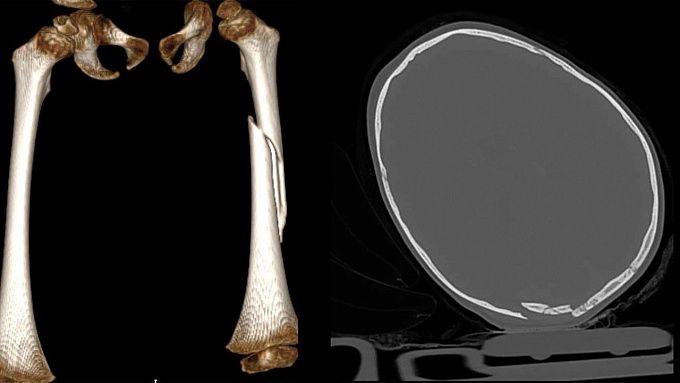

фото: ДРКБ

Трехлетний ребенок, выпавший из окна четвертого этажа на ул. Лебедева, находится в крайне тяжелом состоянии. Об этом сообщили в ДРКБ.

У ребенка – сочетанная травма: черепно-мозговая и перелом бедренной кости. Сейчас он находится в отделении анестезиологии и реанимации. Врачи оказывают всю необходимую помощь, состояние маленького пациента крайне тяжелое.